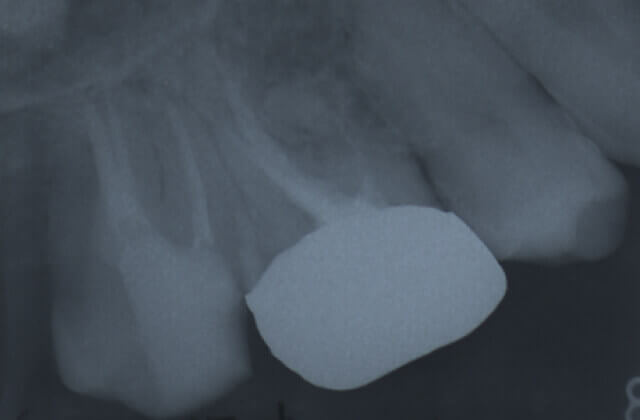

被せ物をした歯の違和感により来院されました

レントゲン写真により経過を確認します

黒い影は骨が溶け膿を持っている